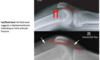

5

Intracapsular NOF